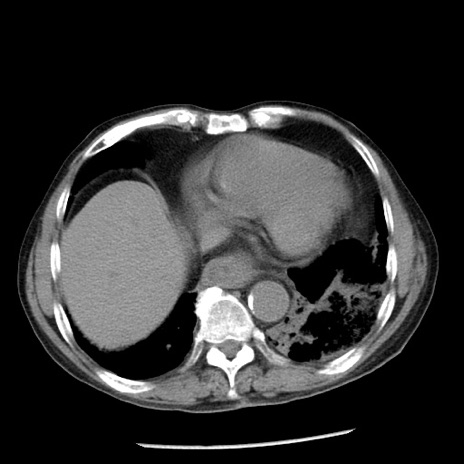

症例26(横断像)

【症例】80歳代男性

【主訴】嘔吐

【現病歴】昨晩2回嘔吐あり、今朝になっても嘔吐あり。来院。

【既往歴】胃潰瘍

【身体所見】意識清明、BT 37.6℃、BP 166/95mmHg、HR 100bpm、SpO2 97%、腹部:平坦・軟、腸蠕動音聴取良好、圧痛なし。

【データ】WBC 21900、CRP 1.46